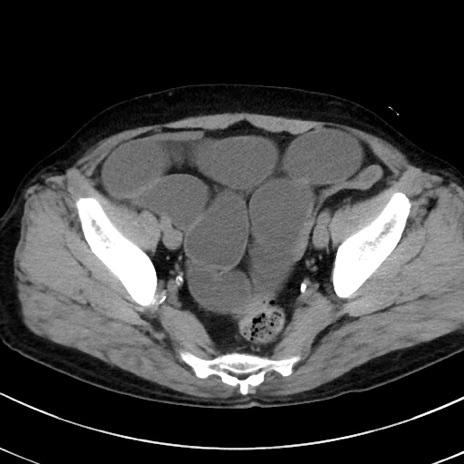

症例38(横断像)

【症例】70歳代 男性

【主訴】腹痛・嘔吐

【現病歴】昨晩より、嘔吐・腹痛あり。今朝になっても嘔吐あり。来院。

【既往歴】心臓バイパス手術、開腹胆摘、腸閉塞

【身体所見】BP 107/71mmHg、HR 116/min、腹部:平坦、軟、下腹部に軽度圧痛あり。反跳痛なし。

【データ】WBC 15100、CRP 0.32

冠状断像